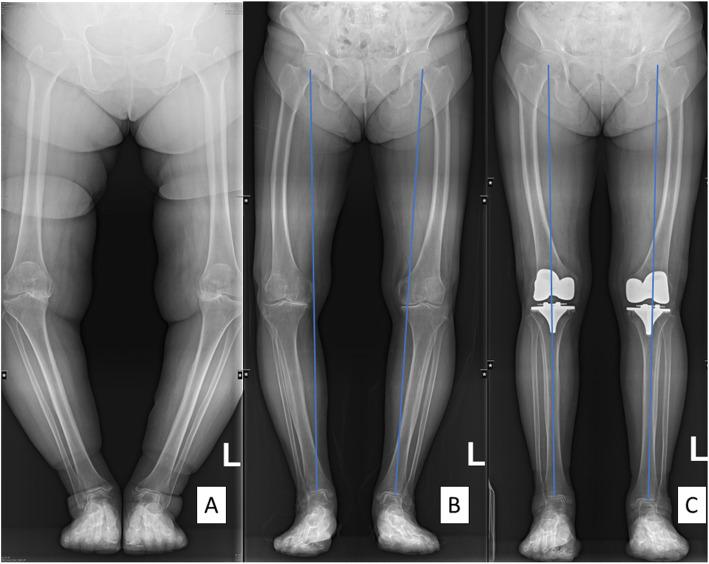

Among 336 patients undergoing bilateral TKAs due to knee osteoarthritis, 29 patients with bilateral lateral femoral bowing of more than 5° were included in this study. Every patient was assigned randomly to PSI on one side and to conventional instrumentation lateralization of the entry point of the femoral IM guide was applied on the other with a goal of neutral mechanical alignment. The assessment of coronal alignment was completed by measuring the hip-knee-ankle (HKA) angle on preoperative and postoperative long film standing radiographs. Coronal and sagittal orientations of femoral and tibial components were assessed on weight-bearing radiographs. The rotational alignment of the femoral component was evaluated using computed tomography.

在336例因膝关节骨关节炎接受双侧TKA的患者中,29例双侧股骨外侧弓形超过5°的患者纳入本研究。每位患者一侧随机分配至PSI,另一侧采用传统器械,将股骨IM导向器入口点进行外侧化,目标是达到中立机械对线。通过术前和术后站立位长片X线片测量髋-膝-踝(HKA)角来完成冠状面对线的评估。在负重X线片上评估股骨和胫骨部件的冠状面和矢状面方向。使用计算机断层扫描评估股骨部件的旋转对线。